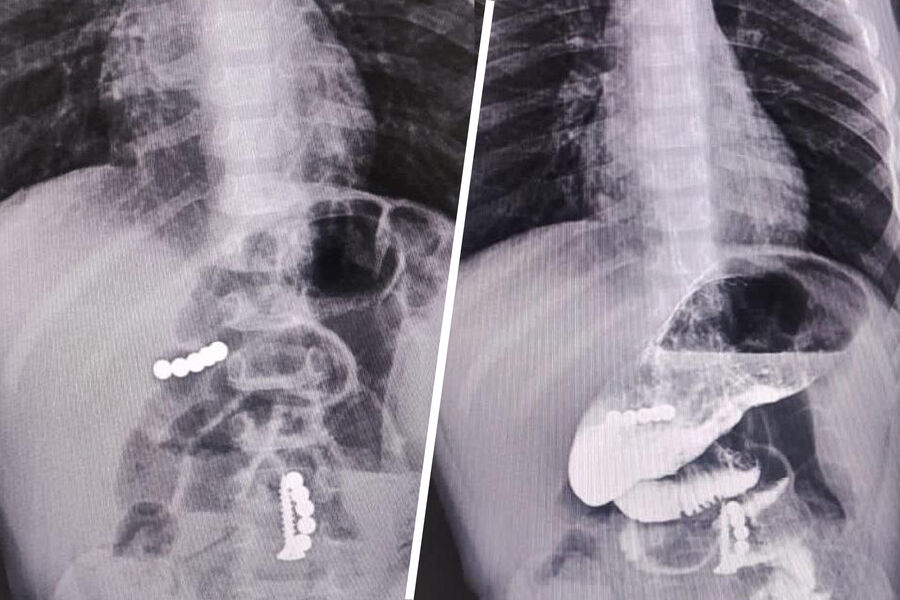

Три магнита и саморез извлекли из кишечника годовалого малыша ставропольские врачи, сообщает пресс-служба Минздрава региона.

«Два магнита диаметром по 5 мм были удалены из полости желудка. Врачи обнаружили, что в толще стенки определяется еще один магнит. После необходимой подготовки ребенку провели лапаротомию», — рассказали в Минздраве.

Еще два магнита и саморез обнаружили в кишечнике, инородные тела слиплись, часть кишечной стенки перфорировалась. Пять дней после операции ребенок находился в отделении реанимации, сейчас его состояние не вызывает у врачей опасений.